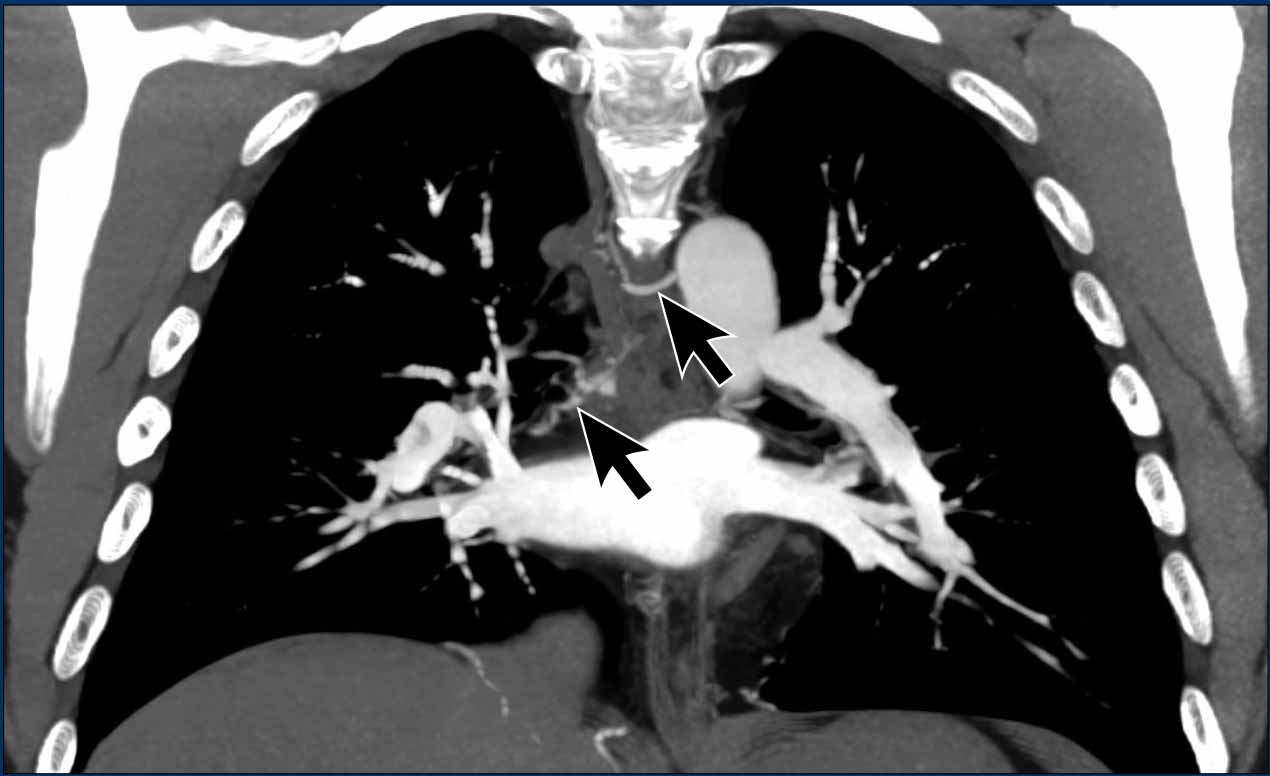

These images are of a patient with pulmonary hypertension secondary to partial anomalous pulmonary venous return (PAPVR).

Imaging Findings

The right lower lobe pulmonary veins are not connected to the left atrium (LA) but instead drain into the superior vena cava (arrows).

Note the bilateral dilatation of the pulmonary arteries, consistent with elevated pulmonary arterial pressure.